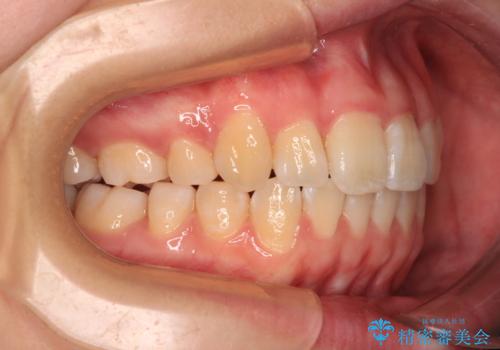

【モニター】八重歯を片側の抜歯矯正で治す メタルブラケット装置

- 八重歯とずれた正中を気にして来院された患者様です。

非抜歯矯正ではデコボコを解消することでより口元が突出する可能性があるため、上顎右右側の小臼歯1本の抜歯を行い、ワイヤー装置による矯正治療を行うこととしました。

お仕事の予定を調整しやすく、平日の昼の時間帯に通院可能であったので、非常にスムーズに治療を進めることができ、1年半で無事に治療を終えることができました。